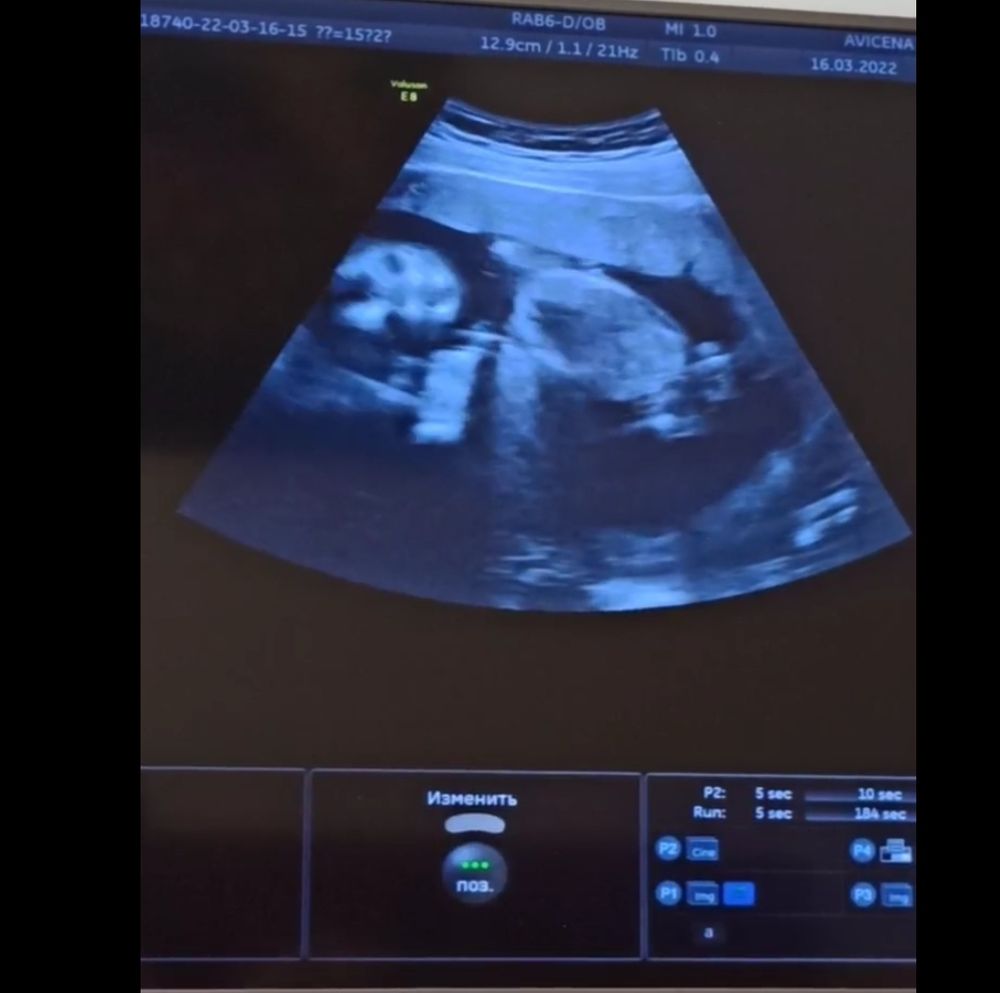

16-ая неделя, наконец-то встретились!

16.03.2022

По профилю на мальчишку похож! Лёгкой вам беременности! Ваша история ещё раз доказывает,что крепкому и здоровому ребенку ничто не может помешать расти и развиваться ;)

Какой необычный интересный ракурс- с личиком) Берегите себя и своего крошку! Прекрасно, что вы все вместе!